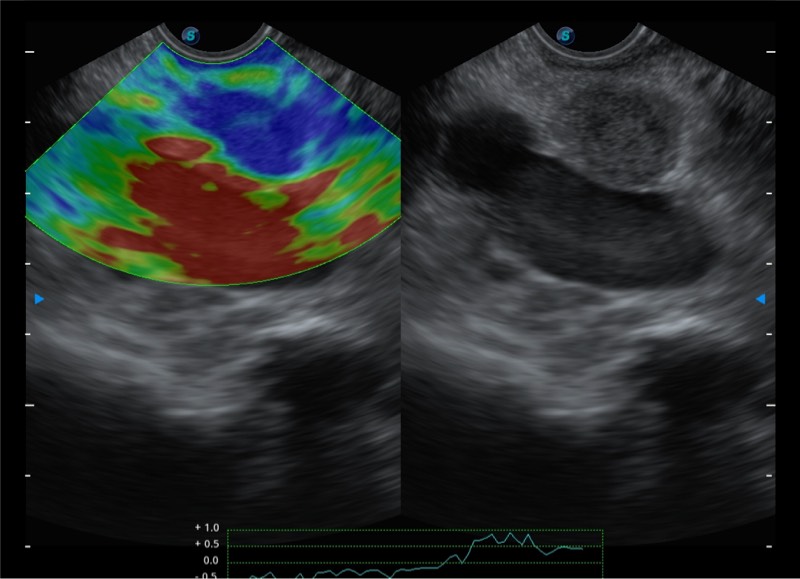

基于二十年的超声技术积累,竞技宝(JJB)官方网站提供了最新一代的独立超声主机,在提供高质量图像的同时满足多学科使用。具备常见多普勒技术并提供弹性成像、声学造影等高端影像技术。新一代传感器具有更强的抗干扰能力并减少图像伪影。